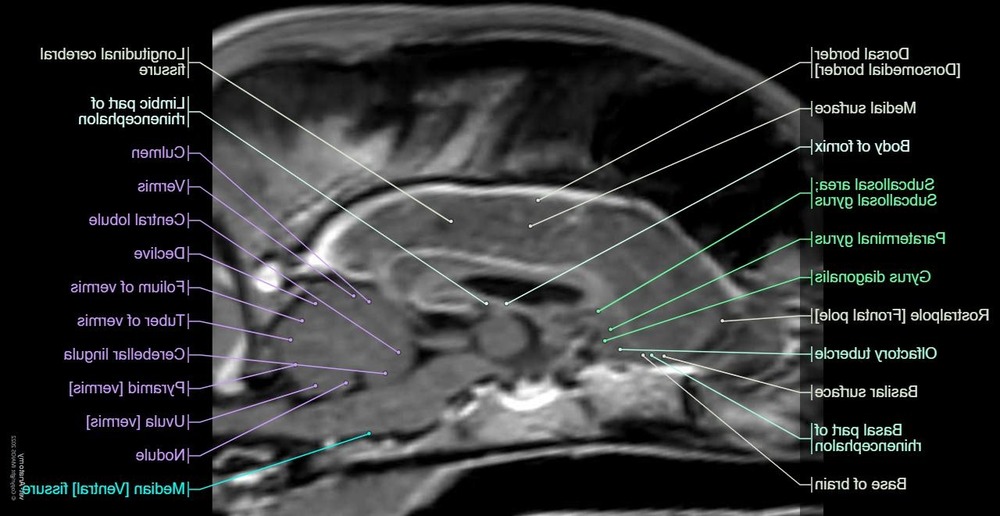

• MRI or CT to look for structural disease such as tumours, strokes, inflammatory changes, or malformations7, 5